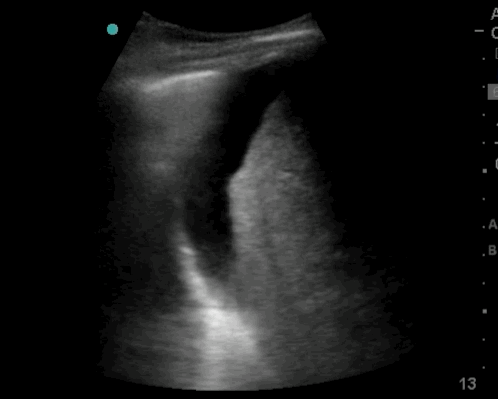

10_Heart_SC

Pericardiel effusion